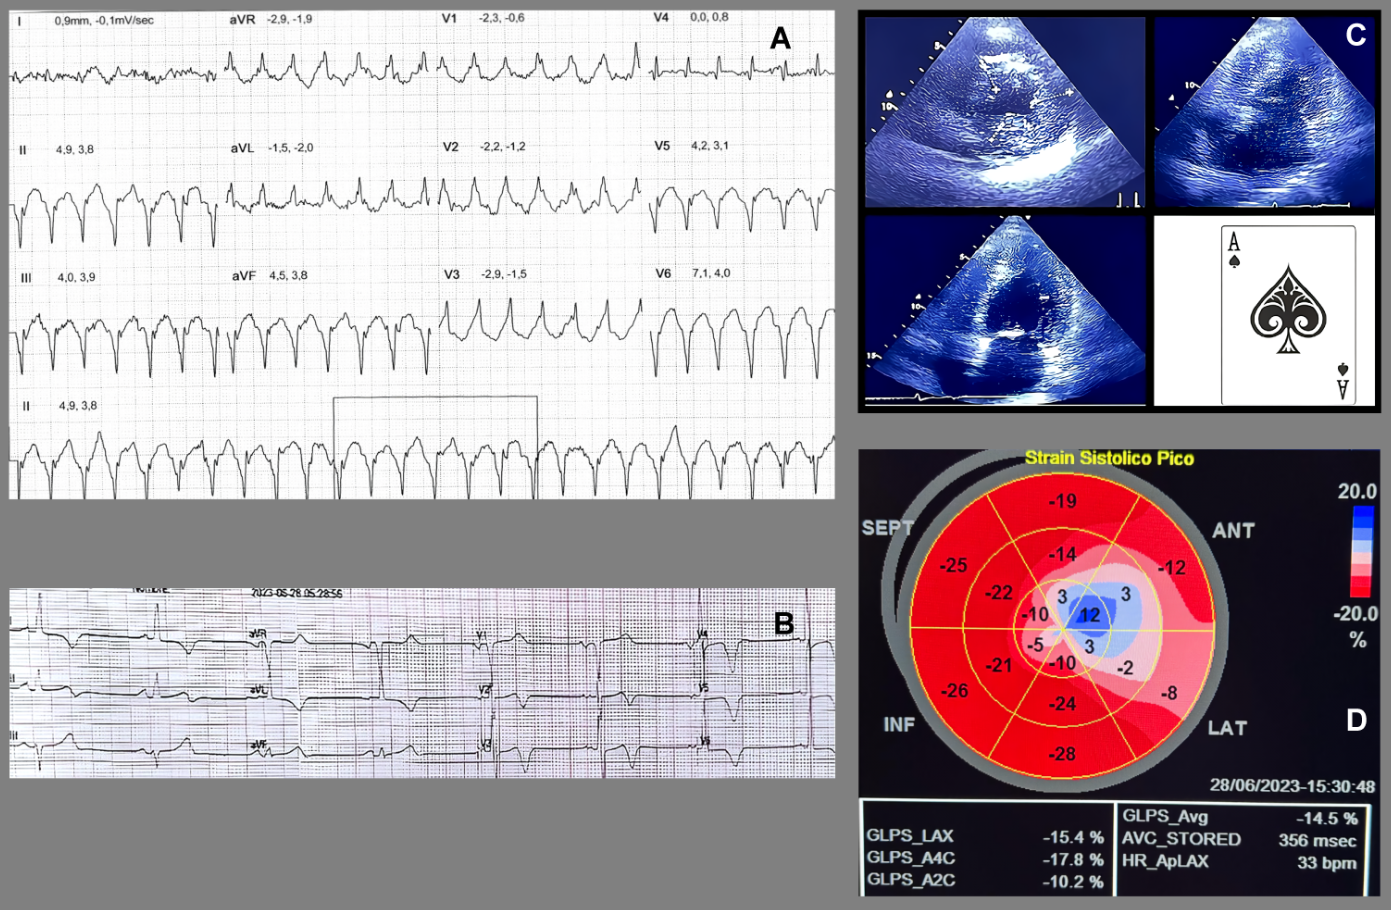

Intramyocardial enhancement was observed in the apical third with an anterior, inferior lateral and septal patchy-diffuse pattern, all compatible with apical hypertrophic cardiomyopathy with preserved biventricular function and a non-ischemic myocardial enhancement pattern, suggestive of diffuse fibrosis in hypertrophic areas of the left ventricle, with a semiquantitative calculation of LV myocardial fibrosis of 52% (Figure 2A). The 3-chamber magnetic resonance (MRI) imaging slice showed a left ventricle (LV) with an end-diastolic volume (EDV) of 63 ml and an end-systole volume (ESV) of 23 ml, with a sign of "ace of spades" due to collapse in systole in the apical third of the ventricle with a maximum thickening at the apical level of 23 mm (Figure 2B). It was decided to perform a left heart catheterization due to electrocardiographic findings and episodes of ventricular tachycardia; this showed coronary arteries without lesions. Due to findings in the stress test of VT and high load of diffuse fibrosis in hypertrophic areas in the MRI, it was decided to take the patient to an electrophysiological study to determine the origin of the arrhythmia and substrate arrhythmic modulation through three-dimensional electroanatomical mapping system. With identification of PVC and focal VT from the mitral postero-septal papillary muscle (Figure 3A), so radiofrequency ablation was performed successfully (Figure 3B). Subsequently, it was decided to place a definitive percutaneous bicameral cardiodesfibrillator to prevent sudden death. The patient tolerated the procedure without complications and was prescribed amiodarone 200 mg orally daily during 3 months. Studies for Fabry disease were requested which were negative, and a panel for MYH7, TNNI3, GLA, MYBPC3, TNNT2, TPM1, MYL2, MYL3, LAMP3, LSAMP, PRKAG2, АСТАА1 gene mutations with negative result.

Figure 3. (A): Reconstruction of the three-dimensional electroanatomical mapping system identifying the focus of "focal monomorphic ventricular tachycardia" in the base of mitral posteroseptal papillary muscle. (B): Radiofrequency lesions in the posteroseptal mitral papillary muscle

Moreover, in recent years predictors of additional arrhythmic events have been described, such as late gadolinium enhancement of the left ventricle > 15%, atrial fibrillation and the presence of LV apical aneurysm [8]. Contrary to prevailing concepts, the course of AHCM is not entirely benign and may be associated with clinical, electrocardiographic and arrhythmogenic abnormalities in the course of its natural long-term course [23]. Various working groups in AHF have detected, by Holter monitoring, the presence of symptomatic and asymptomatic non sustained VT in 18% and 5%, respectively. AF in 12%, and VF in 1%. Monomorphic VT occurs more often in the presence of aneurysms, possibly related to reentry around the aneurysm [24]. In our case, the typical electrocardiographic findings of Yamaguchi syndrome were present (nonischemic large negative T waves), and we were able to detect the sign of the "Ace of Spades" both in MRI and echocardiography. Apical compromise was also found in the strain technique [25]. During the electrophysiological study, focal VT was detected at the level of the postero-septal papillary muscle of the left ventricle. Sustained and non-sustained VT originating in the papillary muscles (Figure 3A – Figure 3B) are uncommon and are triggered by focal mechanisms that include increased cardiac automaticity or PVCs [26]. Treatment, in addition to genetic counseling and prevention of sudden death, consists of symptom control with the use of beta-blockers and non-dihydropyridine calcium antagonists [21]. Our patient received amiodarone after arrhythmic substrate ablation with improvement of symptomatology. Although the HCM risk-SCD was no higher than > 4%, Implantable Cardioverter Desfibrillator (ICD) placement as primary prevention was reasonable due to > 50% fibrosis in the apical segments, the presence of VT, and a maximum wall thickness of 23 mm. We emphasize that there are no predictive models applicable to AHCM, so the risk of this entity could be underestimated with conventional criteria for HCM.